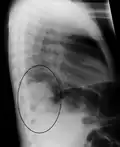

Right upper lobe pneumonia as marked by the circle. -

Right lower lobe pneumonia as seen on a lateral CXR